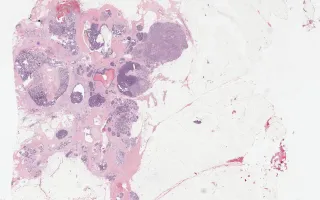

Breast, Adenoid cystic carcinoma, H&E stain

Adenoid cystic carcinoma is a rare type of breast cancer. This tumour is morphologically identical to its counterpart in the salivary gland. Classically, this tumour has a good prognosis even though it is usually triple negative with regards to receptor status.

The differential diagnosis includes collagenous spherulosis, cribriform DCIS, and cribriform carcinoma. Adenoid cystic carcinoma, in contrast to these other entities, is characterized by a dual-cell population: –a ductal-luminal and myoepithelial-basaloid. The ductal component forms true lumina, while the myoepithelial component forms characteristic cylinders with eosinophilic basement membrane-like material. The overall architecture can be cribriform, trabecular, or solid. A CD117 stain highlights the dual cell population; however, CD117 can also be positive in other forms of breast carcinoma.

This slide shows H&E stain, see Related Content for CD117 stain.